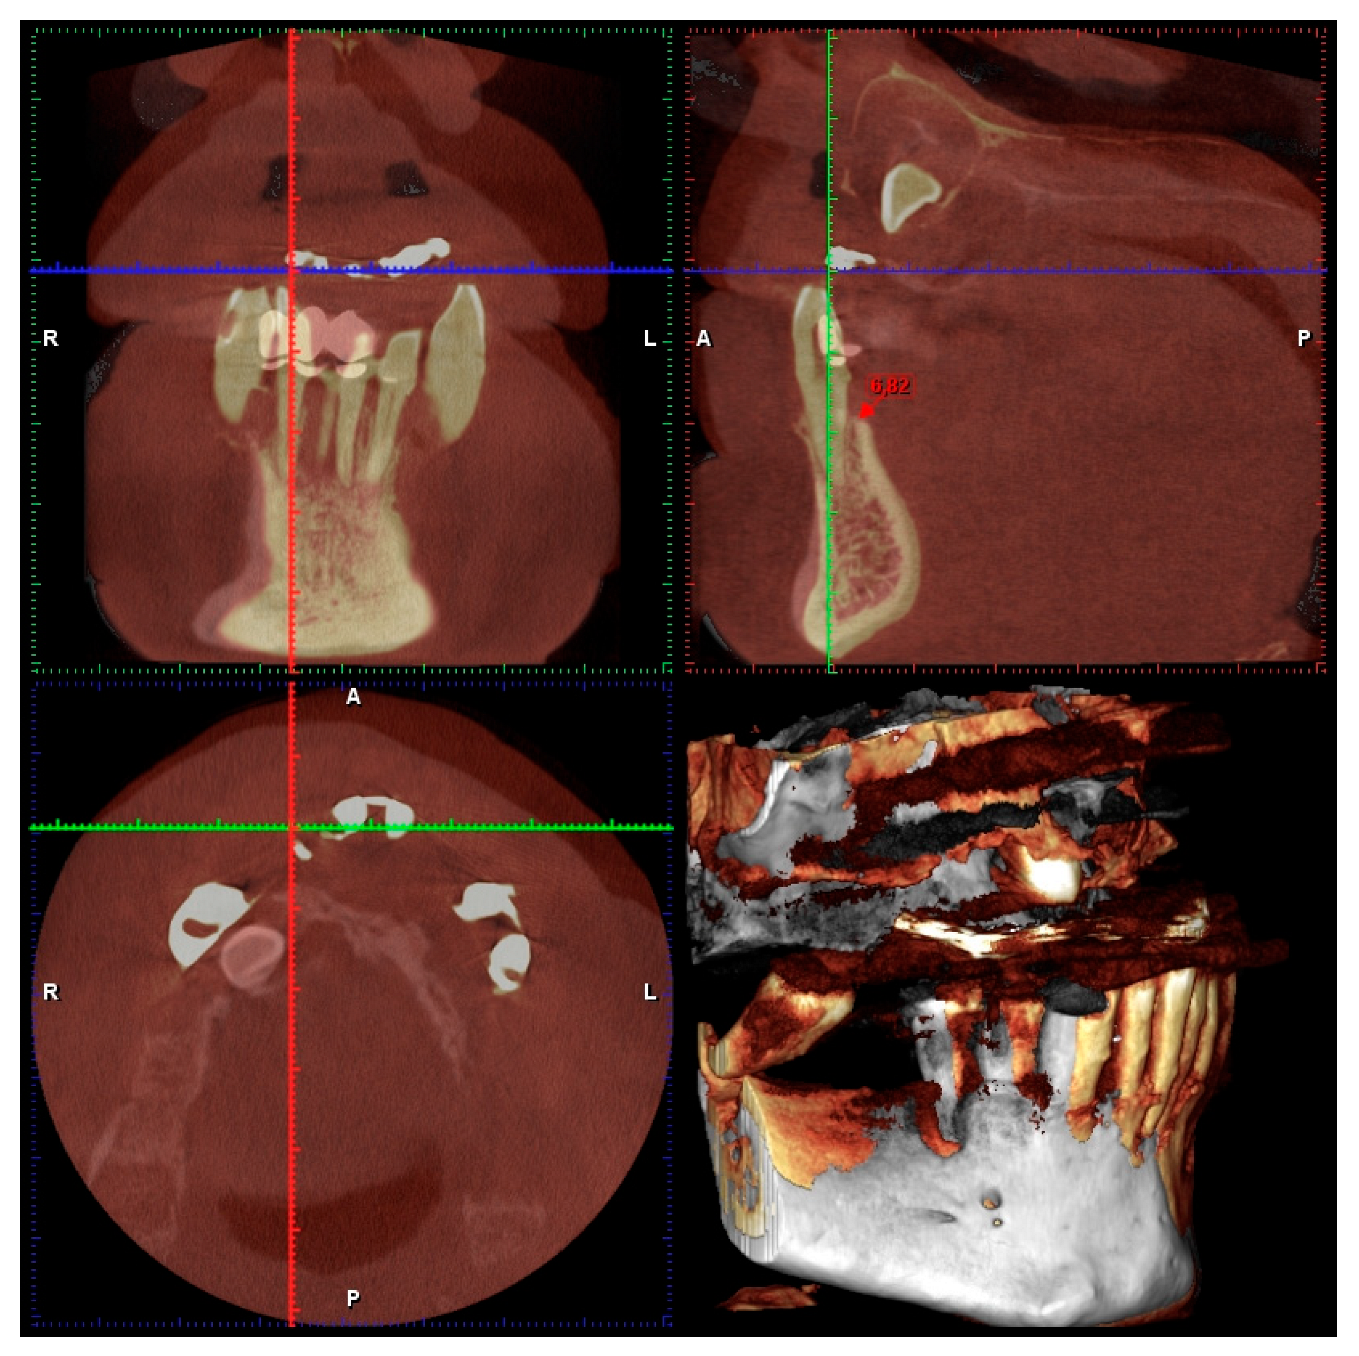

- Presence of hard lamina as evaluated through endoral X-ray;

- Periodontal probing to assess the presence of the buccal plate.